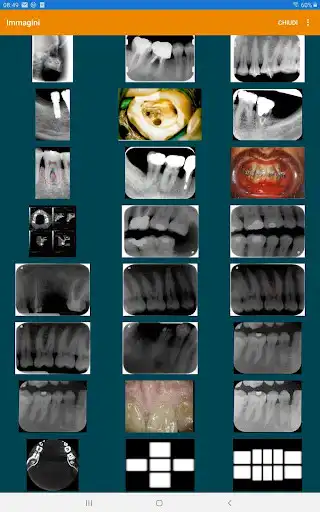

SCREENSHOTS

Uno, il software gestionale per lo studio odontoiatrico sviluppato dalla Divisione informatica Dental Trey, entra nello store Android: con questa applicazione potrai comunicare al meglio con il tuo paziente.

Scopri com semplice aprire le immagini e le sistematiche di ogni paziente e dialogare attraverso gli strumenti di editing messi a disposizione.